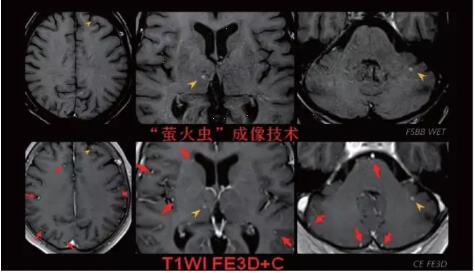

見所未見 微小腫瘤無處遁藏——

“螢火蟲”成像技術(shù) 顱內(nèi)腫瘤微小病灶檢出新發(fā)現(xiàn)

此技術(shù)主要用于神經(jīng)系統(tǒng)惡性腫瘤,以及其他腫瘤腦轉(zhuǎn)移瘤篩查。傳統(tǒng)情況下做腫瘤腦轉(zhuǎn)移篩查,很容易漏掉5mm以下小病灶,臨床發(fā)現(xiàn)后干預(yù)治療比較晚,要實現(xiàn)2mm高空間分辨率和超薄層全腦掃描在保證信噪比的情況下需要很長時間大概十多分鐘,而且薄層增強(qiáng)序列顱內(nèi)血管呈高亮信號,會干擾顱內(nèi)小病灶的觀察,血管和小病灶區(qū)分困難。佳能”螢火蟲”成像技術(shù)既可以實現(xiàn)高空間分辨率和超薄層(最薄可實現(xiàn)0.2mm)全腦掃描,掃描時間短,2-3分鐘即可實現(xiàn)全腦3D掃描,同時避免了血管高亮信號的干擾,對顱內(nèi)原發(fā)或繼發(fā)的微小腫瘤檢查有重大意義。“螢火蟲”成像技術(shù)具有磁敏感效應(yīng),對于亞急性血敏感敏感,可以區(qū)分出血和強(qiáng)化的腫瘤。